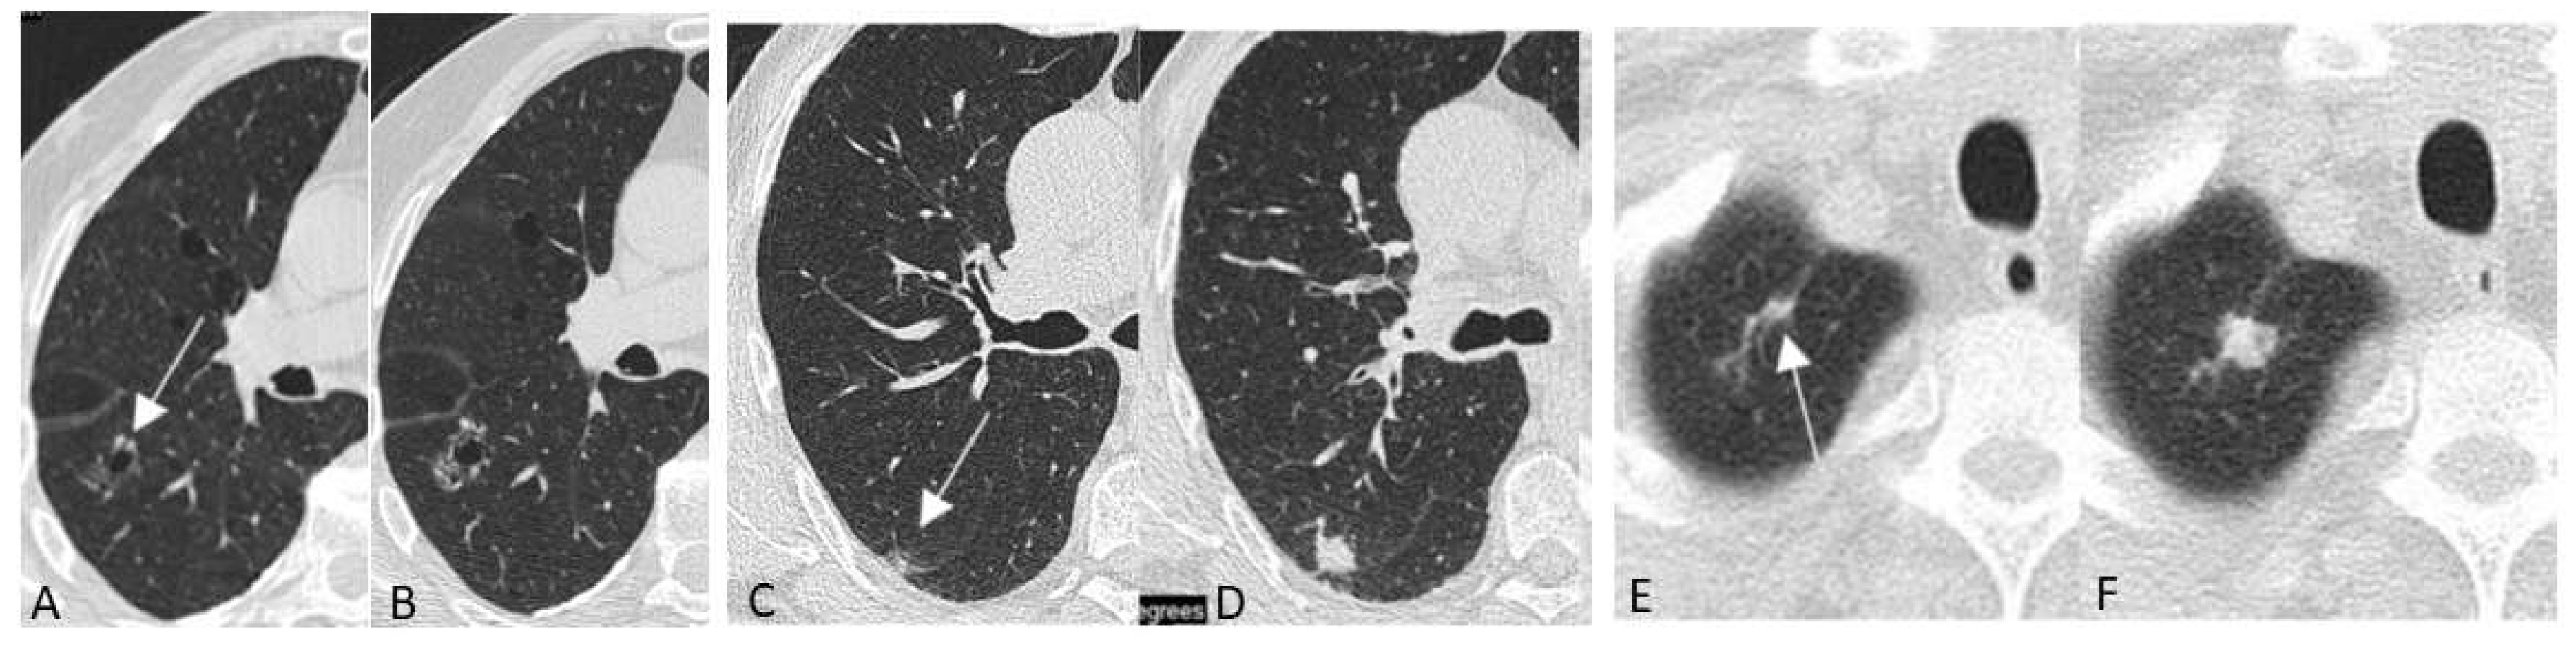

- Mascalchi, M.; Picozzi, G.; Falchini, M.; Vella, A.; Diciotti, S.; Carrozzi, L.; Pegna, A.L.; Falaschi, F. Initial LDCT appearance of incident lung cancers in the ITALUNG trial. Eur. J. Radiol. 2014, 83, 2080–2086. [Google Scholar] [CrossRef]

- Mascalchi, M.; Attinà, D.; Bertelli, E.; Falchini, M.; Vella, A.; Pegna, A.L.; Ambrosini, V.; Zompatori, M. Lung cancer associated with cystic airspaces. J. Comput. Assist. Tomogr. 2015, 39, 102–108. [Google Scholar] [CrossRef] [PubMed]